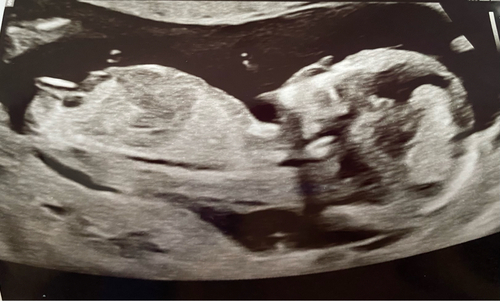

Deze echo eergisteren bij 13+5, heb sterk het gevoel een meisje door deze nub! Zaterdag gaan we horen wat het wordt!